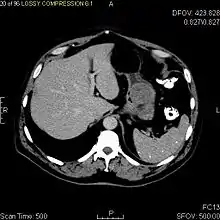

Радиологические исследования

Радиологические исследования используются для уточнения локализации новообразования, выявления признаков инвазии и метастазирования. Проявления ГИСО варьируют в зависимости от размера опухоли и поражённого органа. Диаметр опухоли может составлять от нескольких миллиметров до более 30 см. Крупные опухоли обычно вызывают клинические проявления, бессимптомные опухоли обычно небольших размеров и имеют лучший прогноз.[3][16] Большие опухоли чаще ведут себя более злокачественно, однако и небольшие ГИСО могут иметь агрессивное течение.[17]

Крупные ГИСО

По мере роста опухоли, она может проецироваться снаружи от органа (экзофитный рост) и/или в просвете органа (интралюминальный рост); чаще всего ГИСО растут экзофитно, таким образом большая часть опухоли располагается в проекции брюшной полости. Если увеличение объёма опухоли опережает рост её кровоснабжения, опухоль может некротизироваться в толще, с формированием центральной зоны жидкостной плотности и кавитацией, что может приводить к изъязвлению и формированию соустья с полостью органа. В этом случае исследование с бариевой взвесью может демонстрировать газ, уровни газ/жидкость или депонирование контрастного препарата в этих областях.[17][18] При КТ с контрастным усилением крупные ГИСО выглядят негомогенно, в связи с неоднородностью структуры опухоли, обусловленной участками некроза, кровоизлияниями и полостями, что радиологически проявляется контрастированием опухоли преимущественно по периферии.[16]

Злокачественность может проявляться локальной инвазией и метастазами, обычно в печень, сальник и брюшину. Однако встречаются случаи метастазирования в кости, плевру, лёгкие и забрюшинное пространство. По сравнению с аденокарциномой желудка или лимфомой желудка/тонкой кишки, злокачественная лимфаденопатия при ГИСО не типична (<10 %).[16] При отсутствии метастазов радиологическими признаками злокачественности являются большие размеры опухоли (>5 cm), гетерогенное контрастирование после введения контрастного препарата и наличие изъязвлений.[3][16][22] Также явно злокачественное поведение (без учёта опухолей со злокачественным потенциалом) реже наблюдается при ГИСО желудка, с отношением доброкачественных опухолей к явно злокачественным 3-5:1.[3] Даже в случае наличия радиологических признаков злокачественности, следует учитывать, что они могут быть обусловлены другой опухолью; окончательный диагноз должен быть установлен иммуногистохимическим методом.

Рентгенографические исследования с барием и компьютерная томография обычно применяются для обследования пациентов с абдоминальными жалобами. Исследования с барием выявляют патологические изменения в 80 % случаев ГИСО.[17] Однако некоторые ГИСО могут располагаться полностью вне просвета органа, что делает невозможным их выявление при исследовании с барием. Даже в случае выявления патологических изменений при рентгенографии с барием, необходимо последующее дообследование методами МРТ или КТ. КТ-исследование проводится с пероральным и внутривенным контрастным усилением, и позволяет визуализировать ГИСО в 87 % случаев[17] Мягкие ткани наиболее контрастны при МРТ, что помогает в выявлении интрамуральных образований. Для оценки васкуляризации опухоли необходимо внутривенное введение контрастного препарата.

Методами выбора в диагностике ГИСО являются КТ и МРТ,[23]:20–21 и, в некоторых случаях, эндоскопическое УЗИ. Томографические методы позволяют уточнить органную принадлежность опухоли (что может быть затруднительно при её больших размерах), визуализировать инвазию в соседние органы, асцит и метастазы.